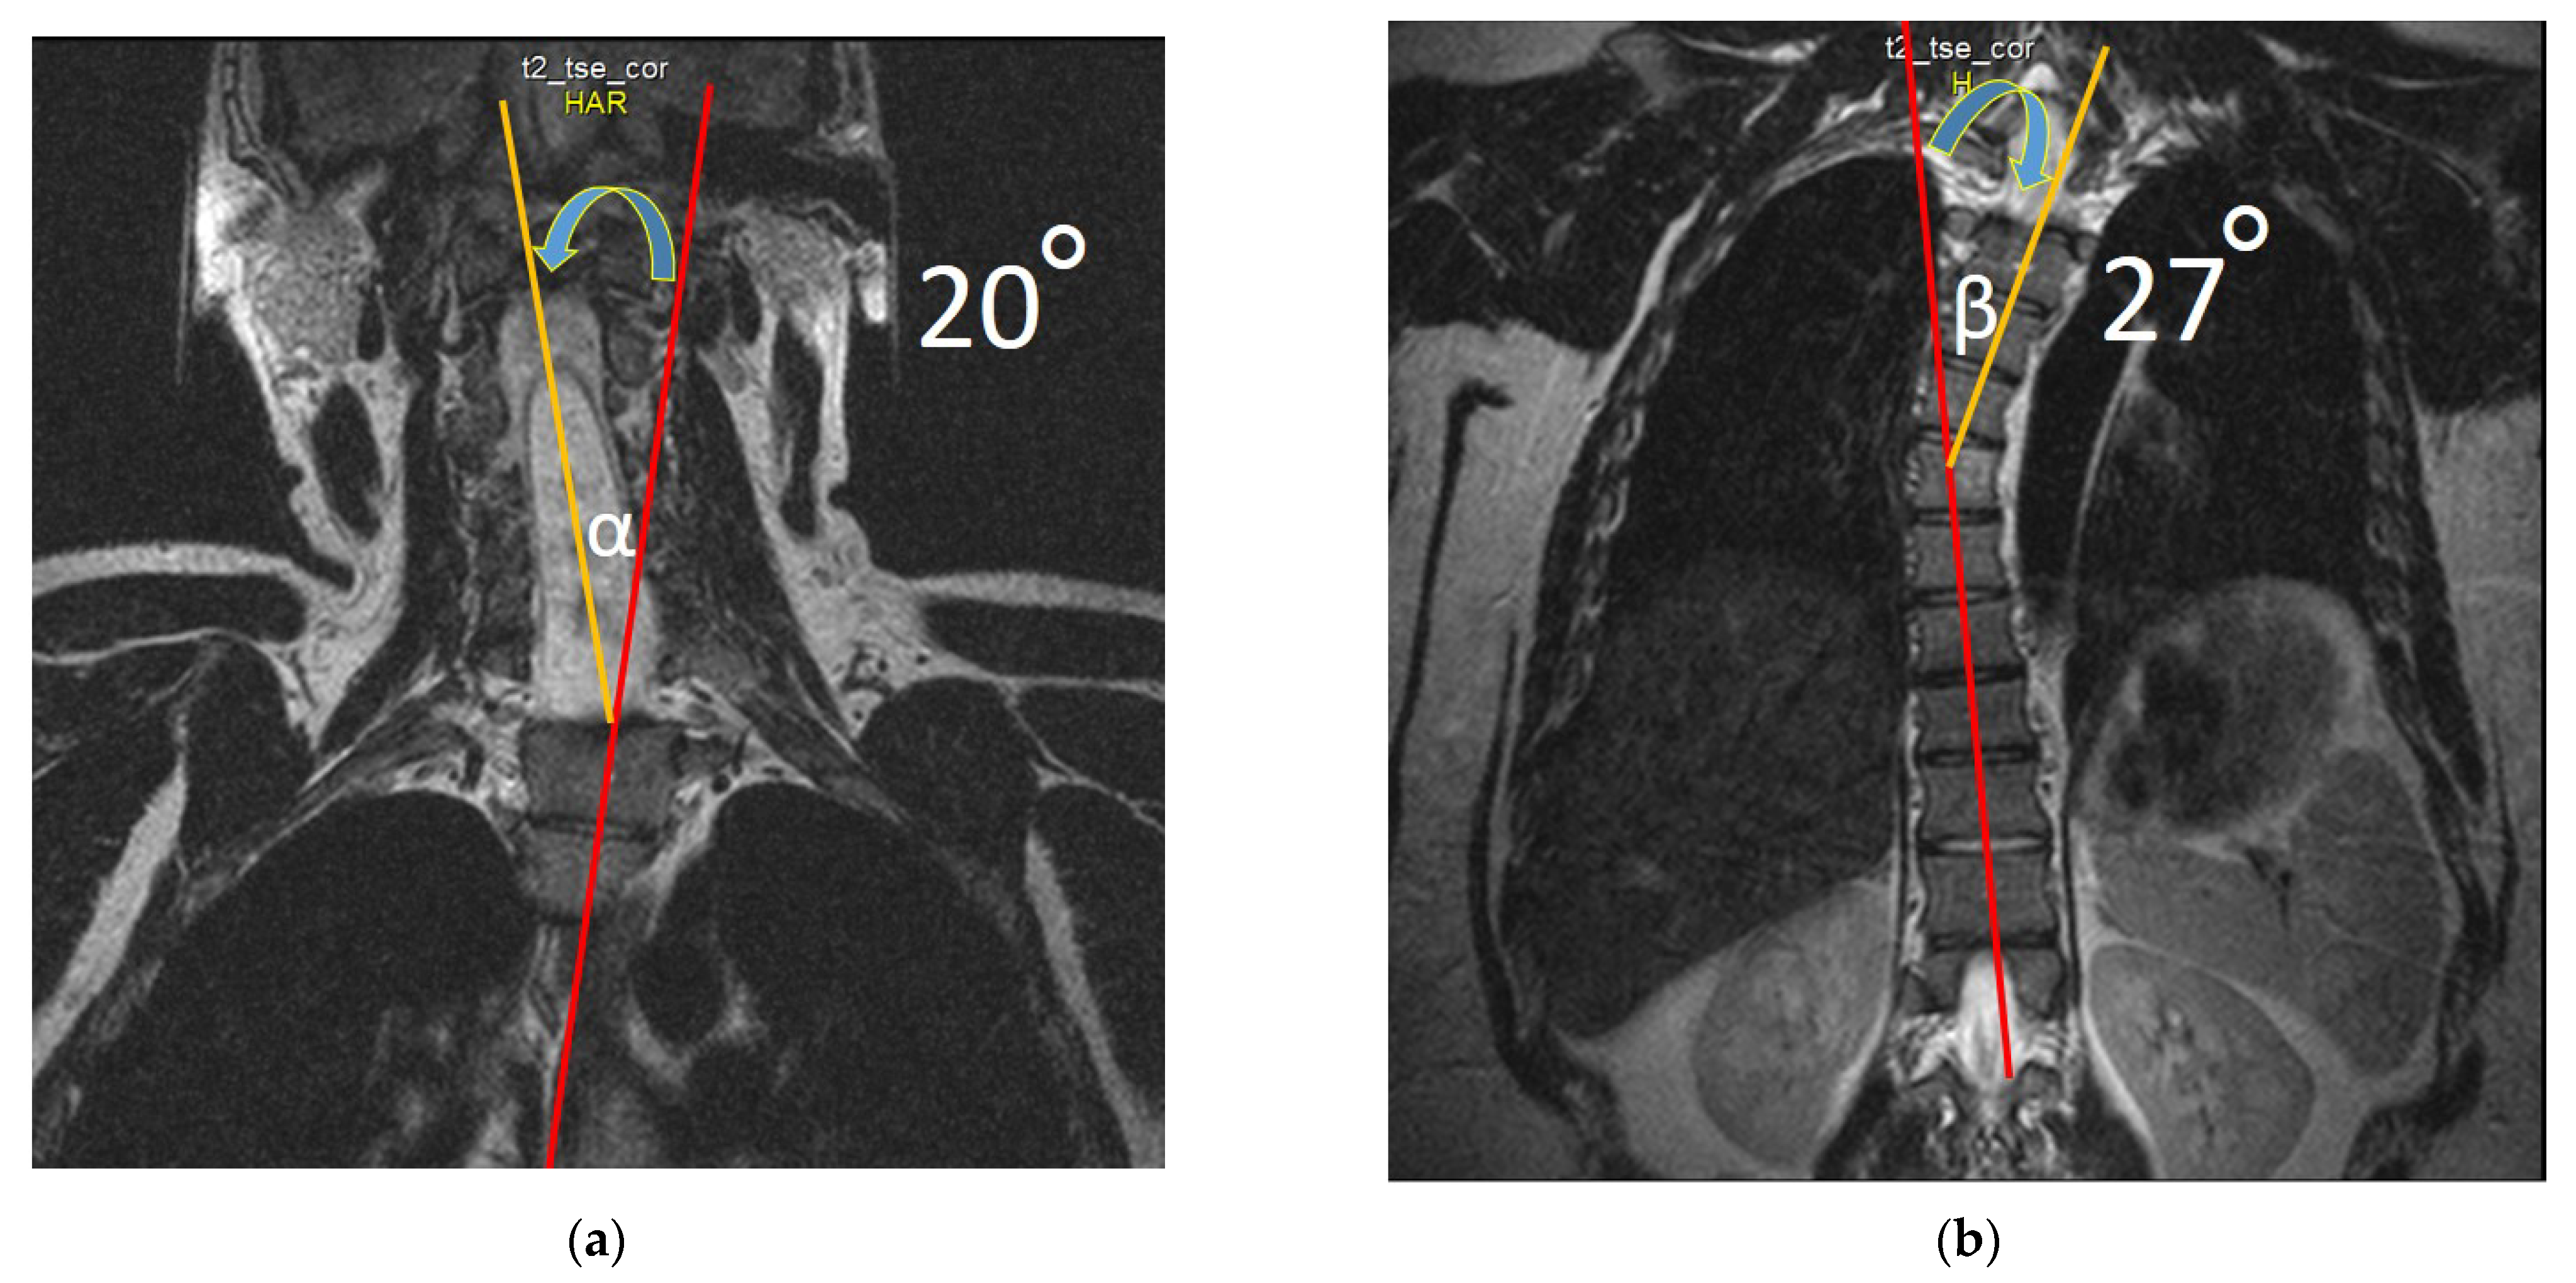

2.4. Neuroimaging